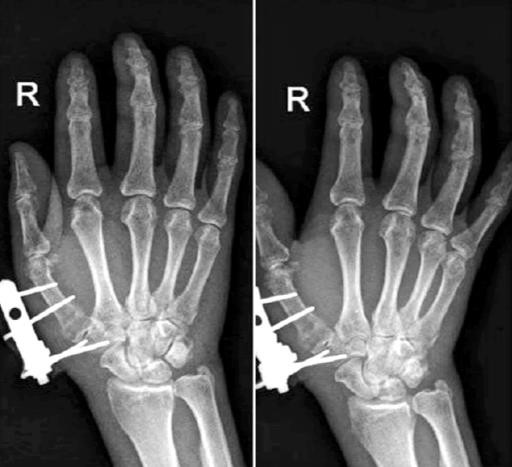

External stabilization system is an effective treatment modality for unstable and compound injuries. With the use of thin smooth wires, which are places away from the injury site in a stable configuration, Joshi’s external stabilizing system (JESS) provides a stable skeletal environment aiding rapid healing of soft tissue wit h establishment of microvascular circulation, immediate active and passive mobilization of the uninjured adjacent joint.[10]

JESS is a simple, versatile and light weight fixation with the added possibility of incorporation of splints or conversion to dynamic mobilization units. JESS provides rigid fixation of bones in which other forms of immobilization are not appropriate e.g., open fracture. It is possible to compress, neutralize or distract a fractures fragment and also allowing aggressive and simultaneous treatment of bone and soft tissue lesions. It is possible to immediately move the proximal and the distal joints, thereby reducing edema, preventing capsular fibrosis, joint stiffness and muscularatrophy.[11]

Closed/open reduction was achieved by traction and manipulation. To maintain reduction, percutaneous Kirschner-wire or Joshi’s external stabilization system were used. Image intensifier (C-arm) was used as a guide for the steps mentioned above. Post-operatively, x-rays were taken to evaluate the fixation. Patients were taught active mobilization of the unaffected fingers, elbow and shoulder from immediate post-op period. Pin tract dressings were done regularly. Patients were called for periodic evaluation at 2 weeks, 4 weeks, 6 weeks and 8 weeks on OPD basis to assess:

Only 66.7% of the patients in group A had stable fixation as compared to 90% of the patients in group B. This difference in stability of the fixation was statistically significant.

About 66.7% of the patients in group A had stable fixation and 90% of the patients in group B had stable fixation which was statistically significant. Naidu et al had reported loosening of K wires in 16% of the cases.[10]